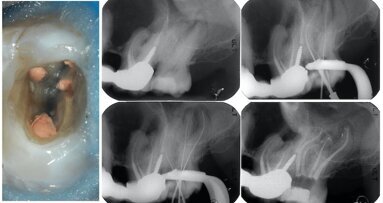

Working length determination is one of the most critical steps of root canal preparation. Measuring the length of the tooth indicates the apical limit of instrumentation and filling. Traditionally, working lengths are determined by taking radiographs. The development of electronic apex locators (EALs) has helped to determine working lengths more accurately and efficiently. An EAL is a device developed to determine the position of the apical foramen by specific differences in the resistance to electrical currents using electrodes positioned at the patient’s lip and attached to the endodontic file. Currently, the use of state-of-the-art apex locators—which measure by impedance differences—makes accurate location of the apical foramen possible, allowing the dental professional to respect the anatomical and morphological limits of the canal, thereby imparting greater predictability to endodontic treatment.

Owing to EALs’ ease of use and high rate of clinical success (around 80–96 per cent) in accurately measuring canal length, the use of EALs is now considered routine in endodontic practice. Their use in all cases, coupled with radiographs, can be considered indispensable. For this reason, several brands of products with differences in operating principle, design, warning sounds produced, screen models and other variables are available on the market.